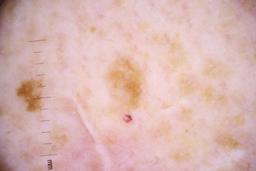

ISIC_4077341

Clinical

| Field | Value |

|---|---|

| acquisition_day | 1 |

| age_approx | 50 |

| anatom_site_1 | Trunk |

| anatom_site_2 | Anterior trunk |

| concomitant_biopsy | False |

| dermoscopic_type | contact non-polarized |

| diagnosis_1 | Benign |

| diagnosis_confirm_type | serial imaging showing no change |

| family_hx_mm | False |

| image_type | dermoscopic |

| lesion_id | IL_9238622 |

| patient_id | IP_1969685 |

| personal_hx_mm | True |

| sex | male |

Columns

Showing first 50 images.